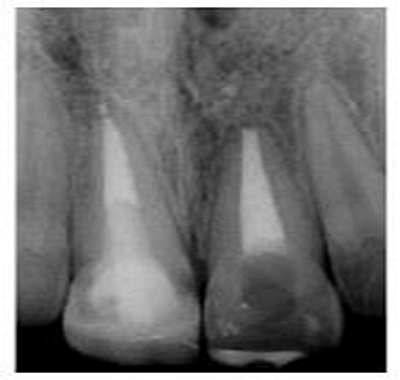

切端則采用透明樹脂,最后使用釉質(zhì)樹脂(Amaris, VOCO, Cuxhaven, Germany)。21的樹脂修復(fù)采用類似的方式。修復(fù)初步成型,拋光,恢復(fù)干燥牙釉質(zhì)的顏色。攝片顯示樁在根管內(nèi)位置合適(圖15)。最后一次復(fù)診精修、拋光充填體,完成治療。